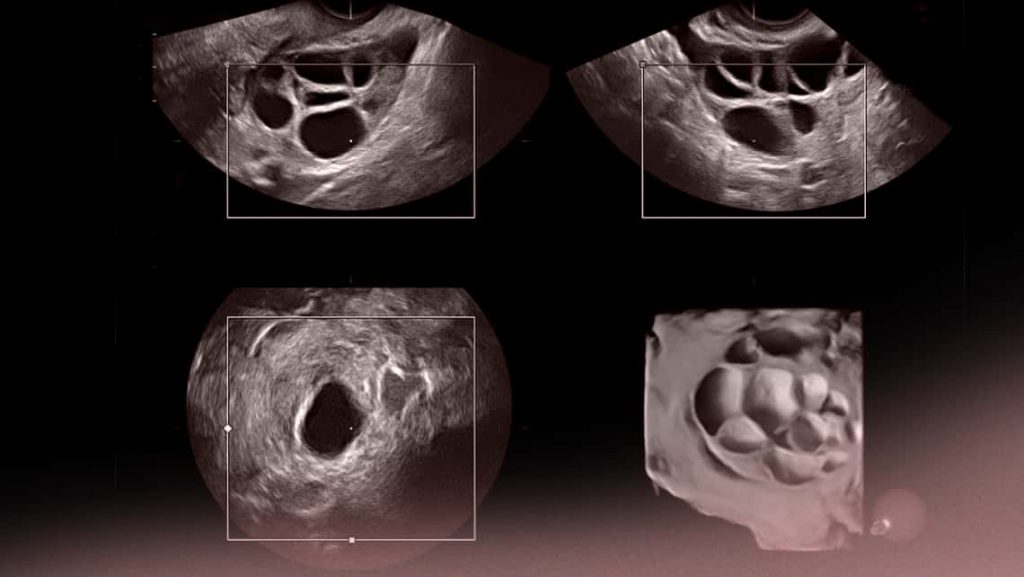

4. Ecografia pelvica: Può essere utilizzata per verificare la presenza di cisti ovariche o anomalie nelle ovaie.